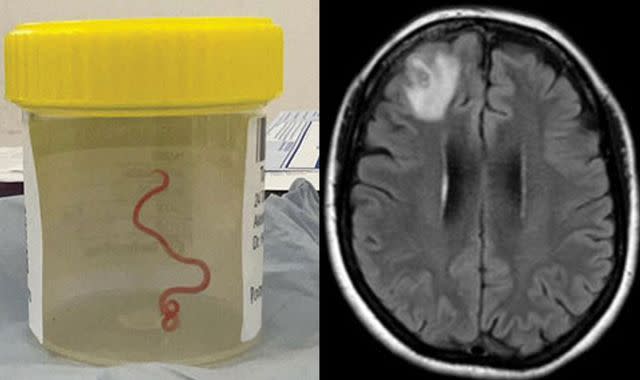

The astounding revelation came to light when doctors removed a “string-like structure” from the damaged frontal lobe of the patient’s brain during a surgery conducted in Canberra last year. Dr. Hari Priya Bandi, the lead surgeon, expressed her shock at the unexpected discovery, stating, “It was definitely not what we were expecting. Everyone was shocked.”

The woman, aged 64, had initially suffered from symptoms such as stomach pain, a persistent cough, and night sweats. Over time, these symptoms escalated to include forgetfulness and depression. Her deteriorating condition led to her hospitalization in late January 2021. A subsequent scan exposed an “atypical lesion within the right frontal lobe of the brain.”

However, it was only during a biopsy performed by Dr. Bandi in June 2022 that the root cause of her condition was unveiled. The surgeon extracted a live parasite that had been dwelling within her brain, possibly for up to two months prior. Remarkably, the woman, who lived near a lake in south-eastern New South Wales state, is reportedly on a promising path to recovery.

The neurosurgeon responsible for the discovery recounted the moment she encountered the worm, describing how she felt a peculiar sensation as she touched the abnormal brain tissue. Dr. Bandi shared, “I pulled it out… and it was happily moving, quite vigorously, outside the brain.” Her findings left the entire operating team stunned.